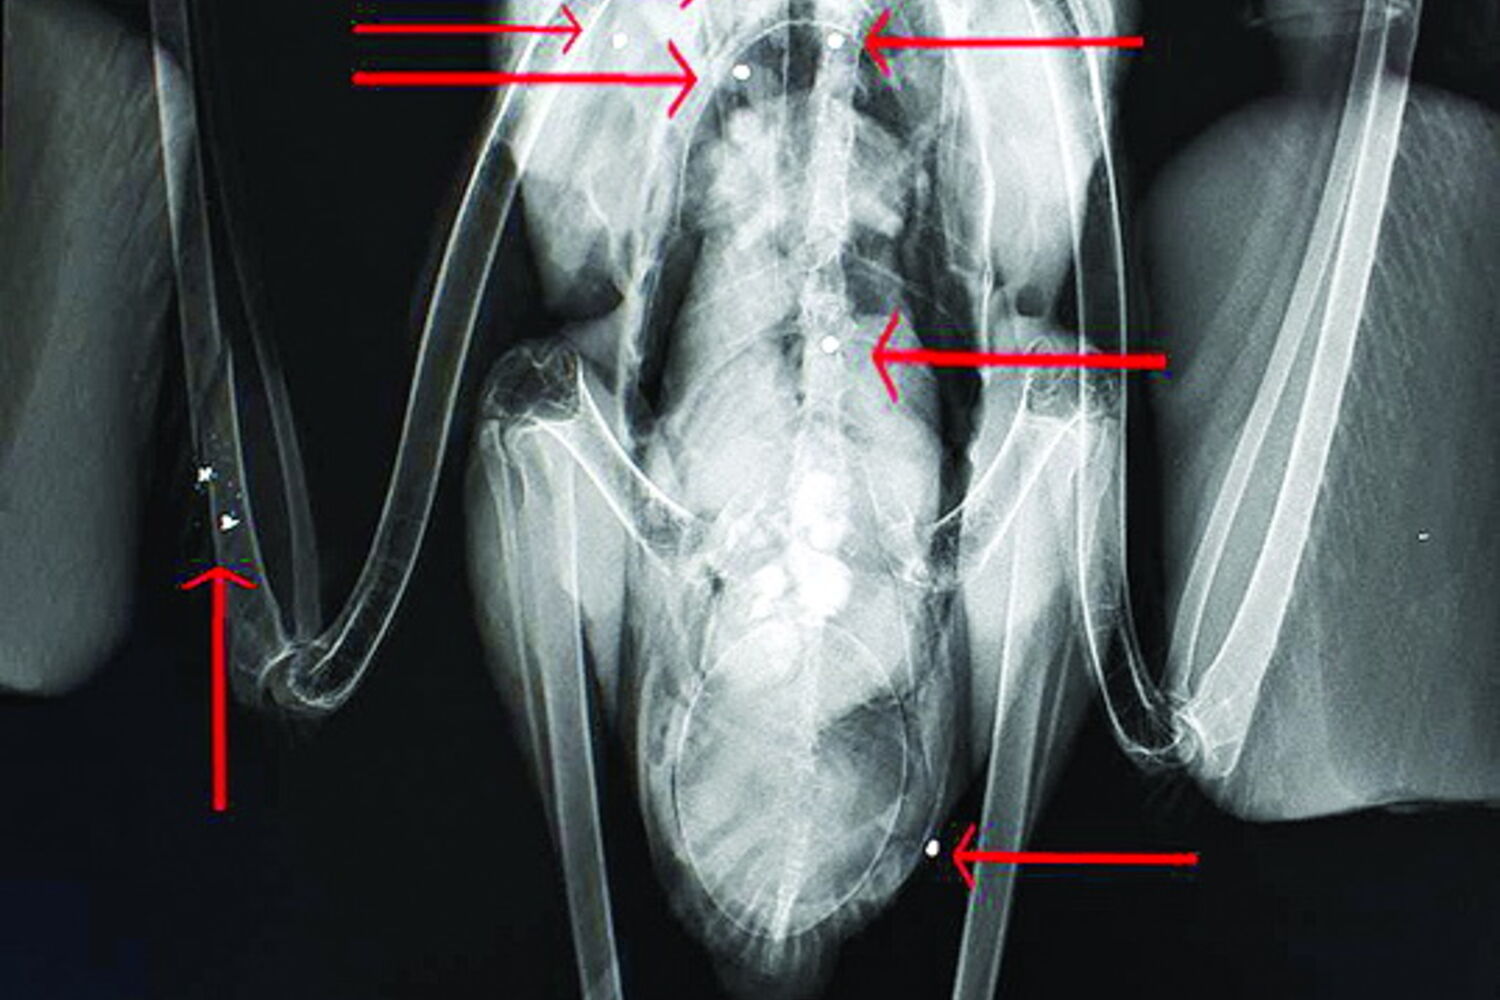

Uma cegonha branca (Ciconia ciconia), com cerca de 4 anos, foi alvejada com 10 chumbos de caçadeira em vários locais do corpo, no passado dia 12 de Abril, no Algarve.

O CM apurou junto da bióloga e coordenadora do (RIAS) Fábia Santos que "quando o animal chegou foi feito imediatamente um exame sistematizado e uma radiografia, onde foi verificado que o animal tinha 10 chumbos de caçadeira, que estava fraturada a asa direita e foi possível verificar a presença de um ovo, que estava afetado parcialmente e foi expulso" pela ave.